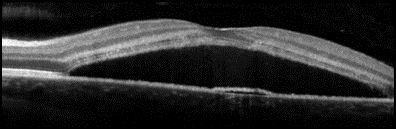

Figuur: Oogscan (OCT scan) van patiënt met CSC (linker afbeelding): een zwarte vochtophoping onder het netvlies (macula). Het witte lijntje daaronder is de pigmentcel-laag (RPE), waar het vocht doorheen lekt. Ter vergelijking de rechter afbeelding van een normaal netvlies.

- Een scan van de lagen van uw netvlies (OCT scan), om de vochtophoping optimaal in beeld te brengen (zie figuur op de vorige pagina).